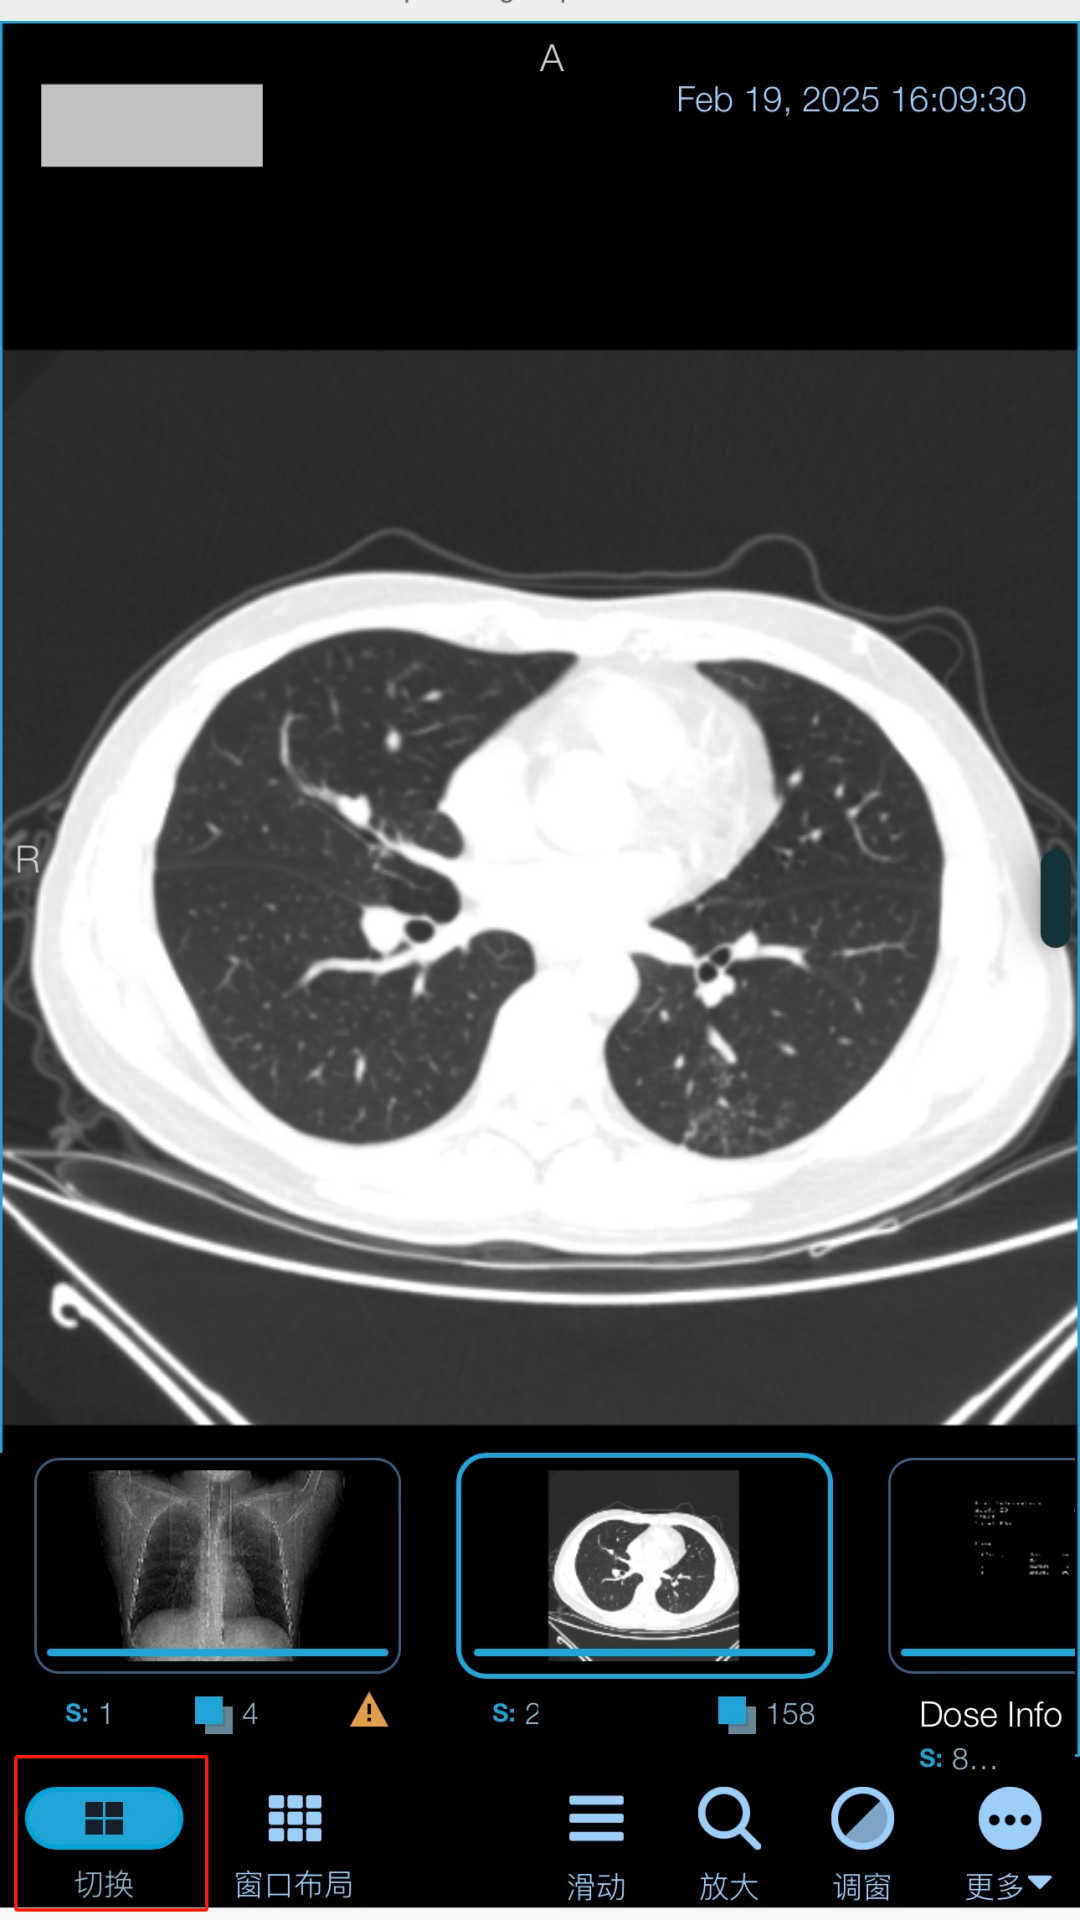

第三步:点击“序列胶片”查看原始胶片记录。

第四步:点击“切换”可查看多张胶片信息,本胶片信息可反复查看,易于长期保存,长按也可保存至手机相册。